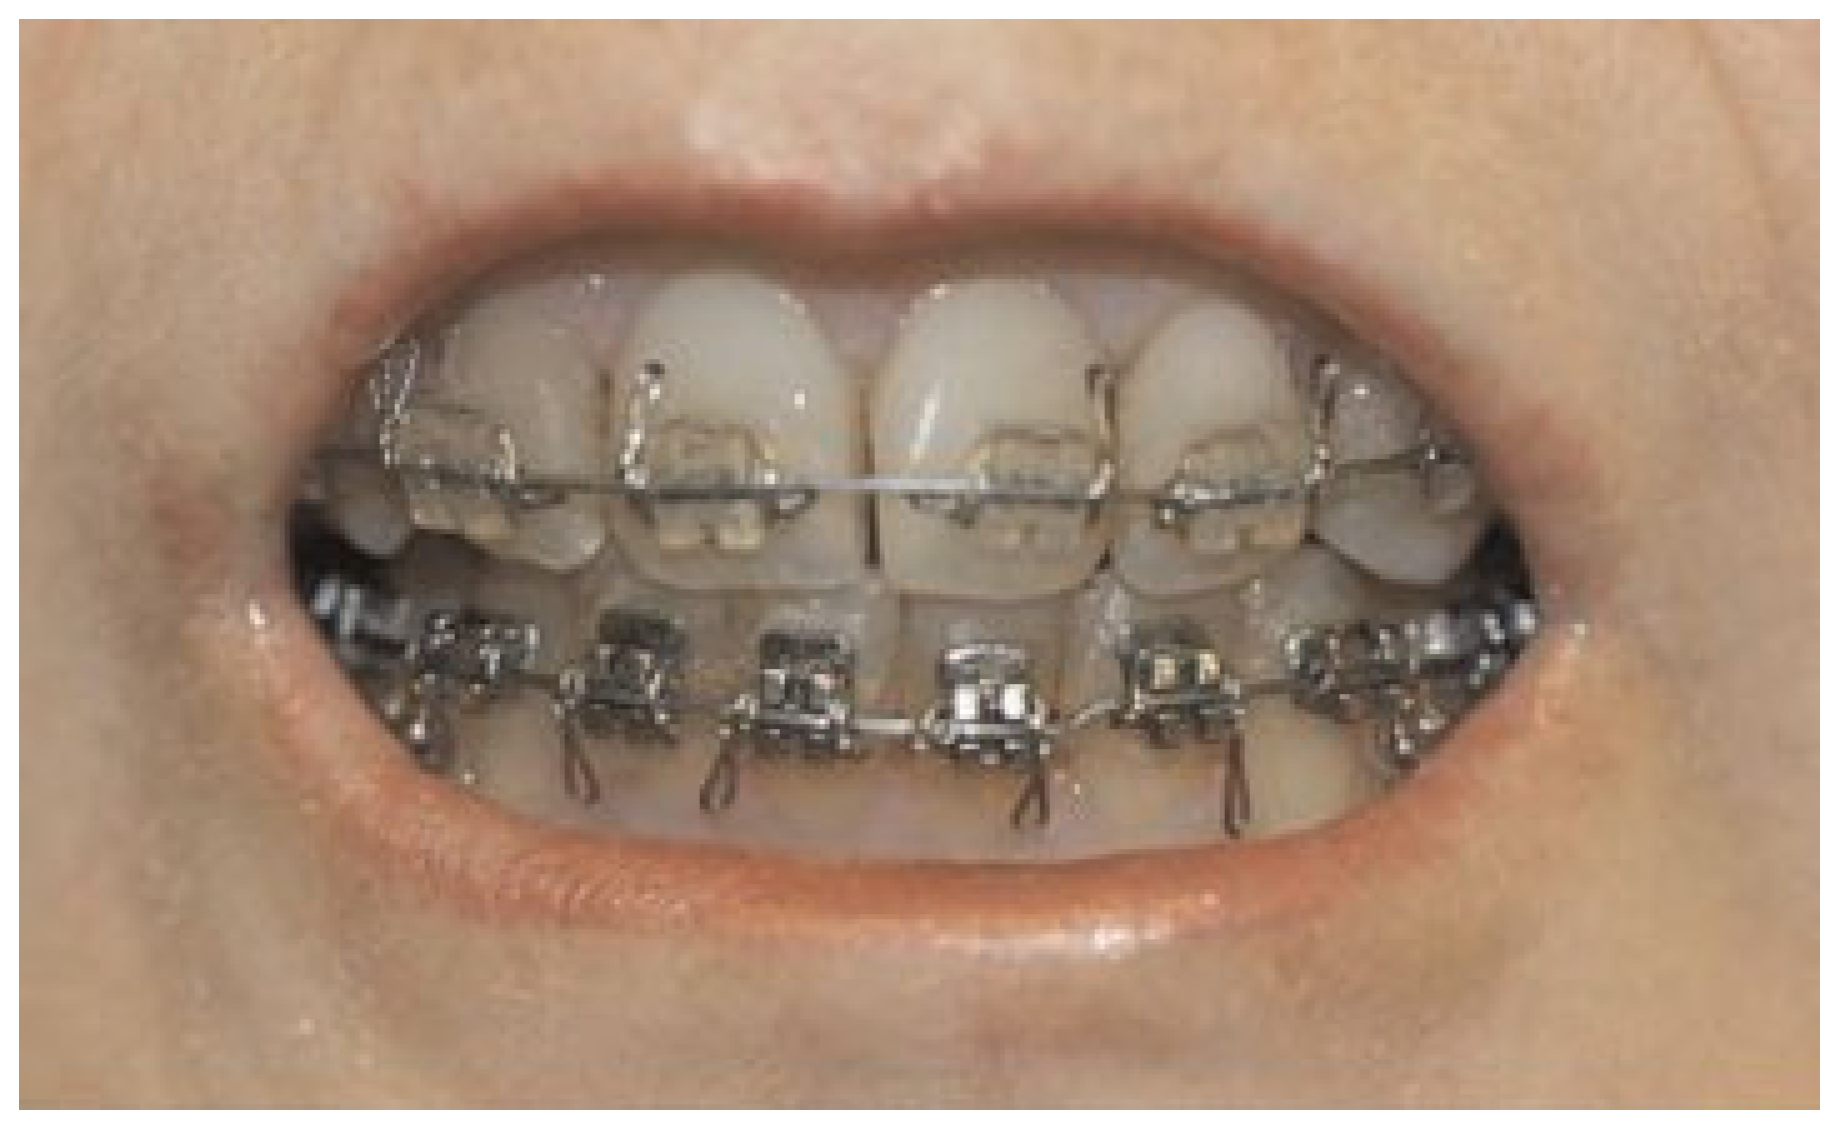

Surgical Treatment

Results